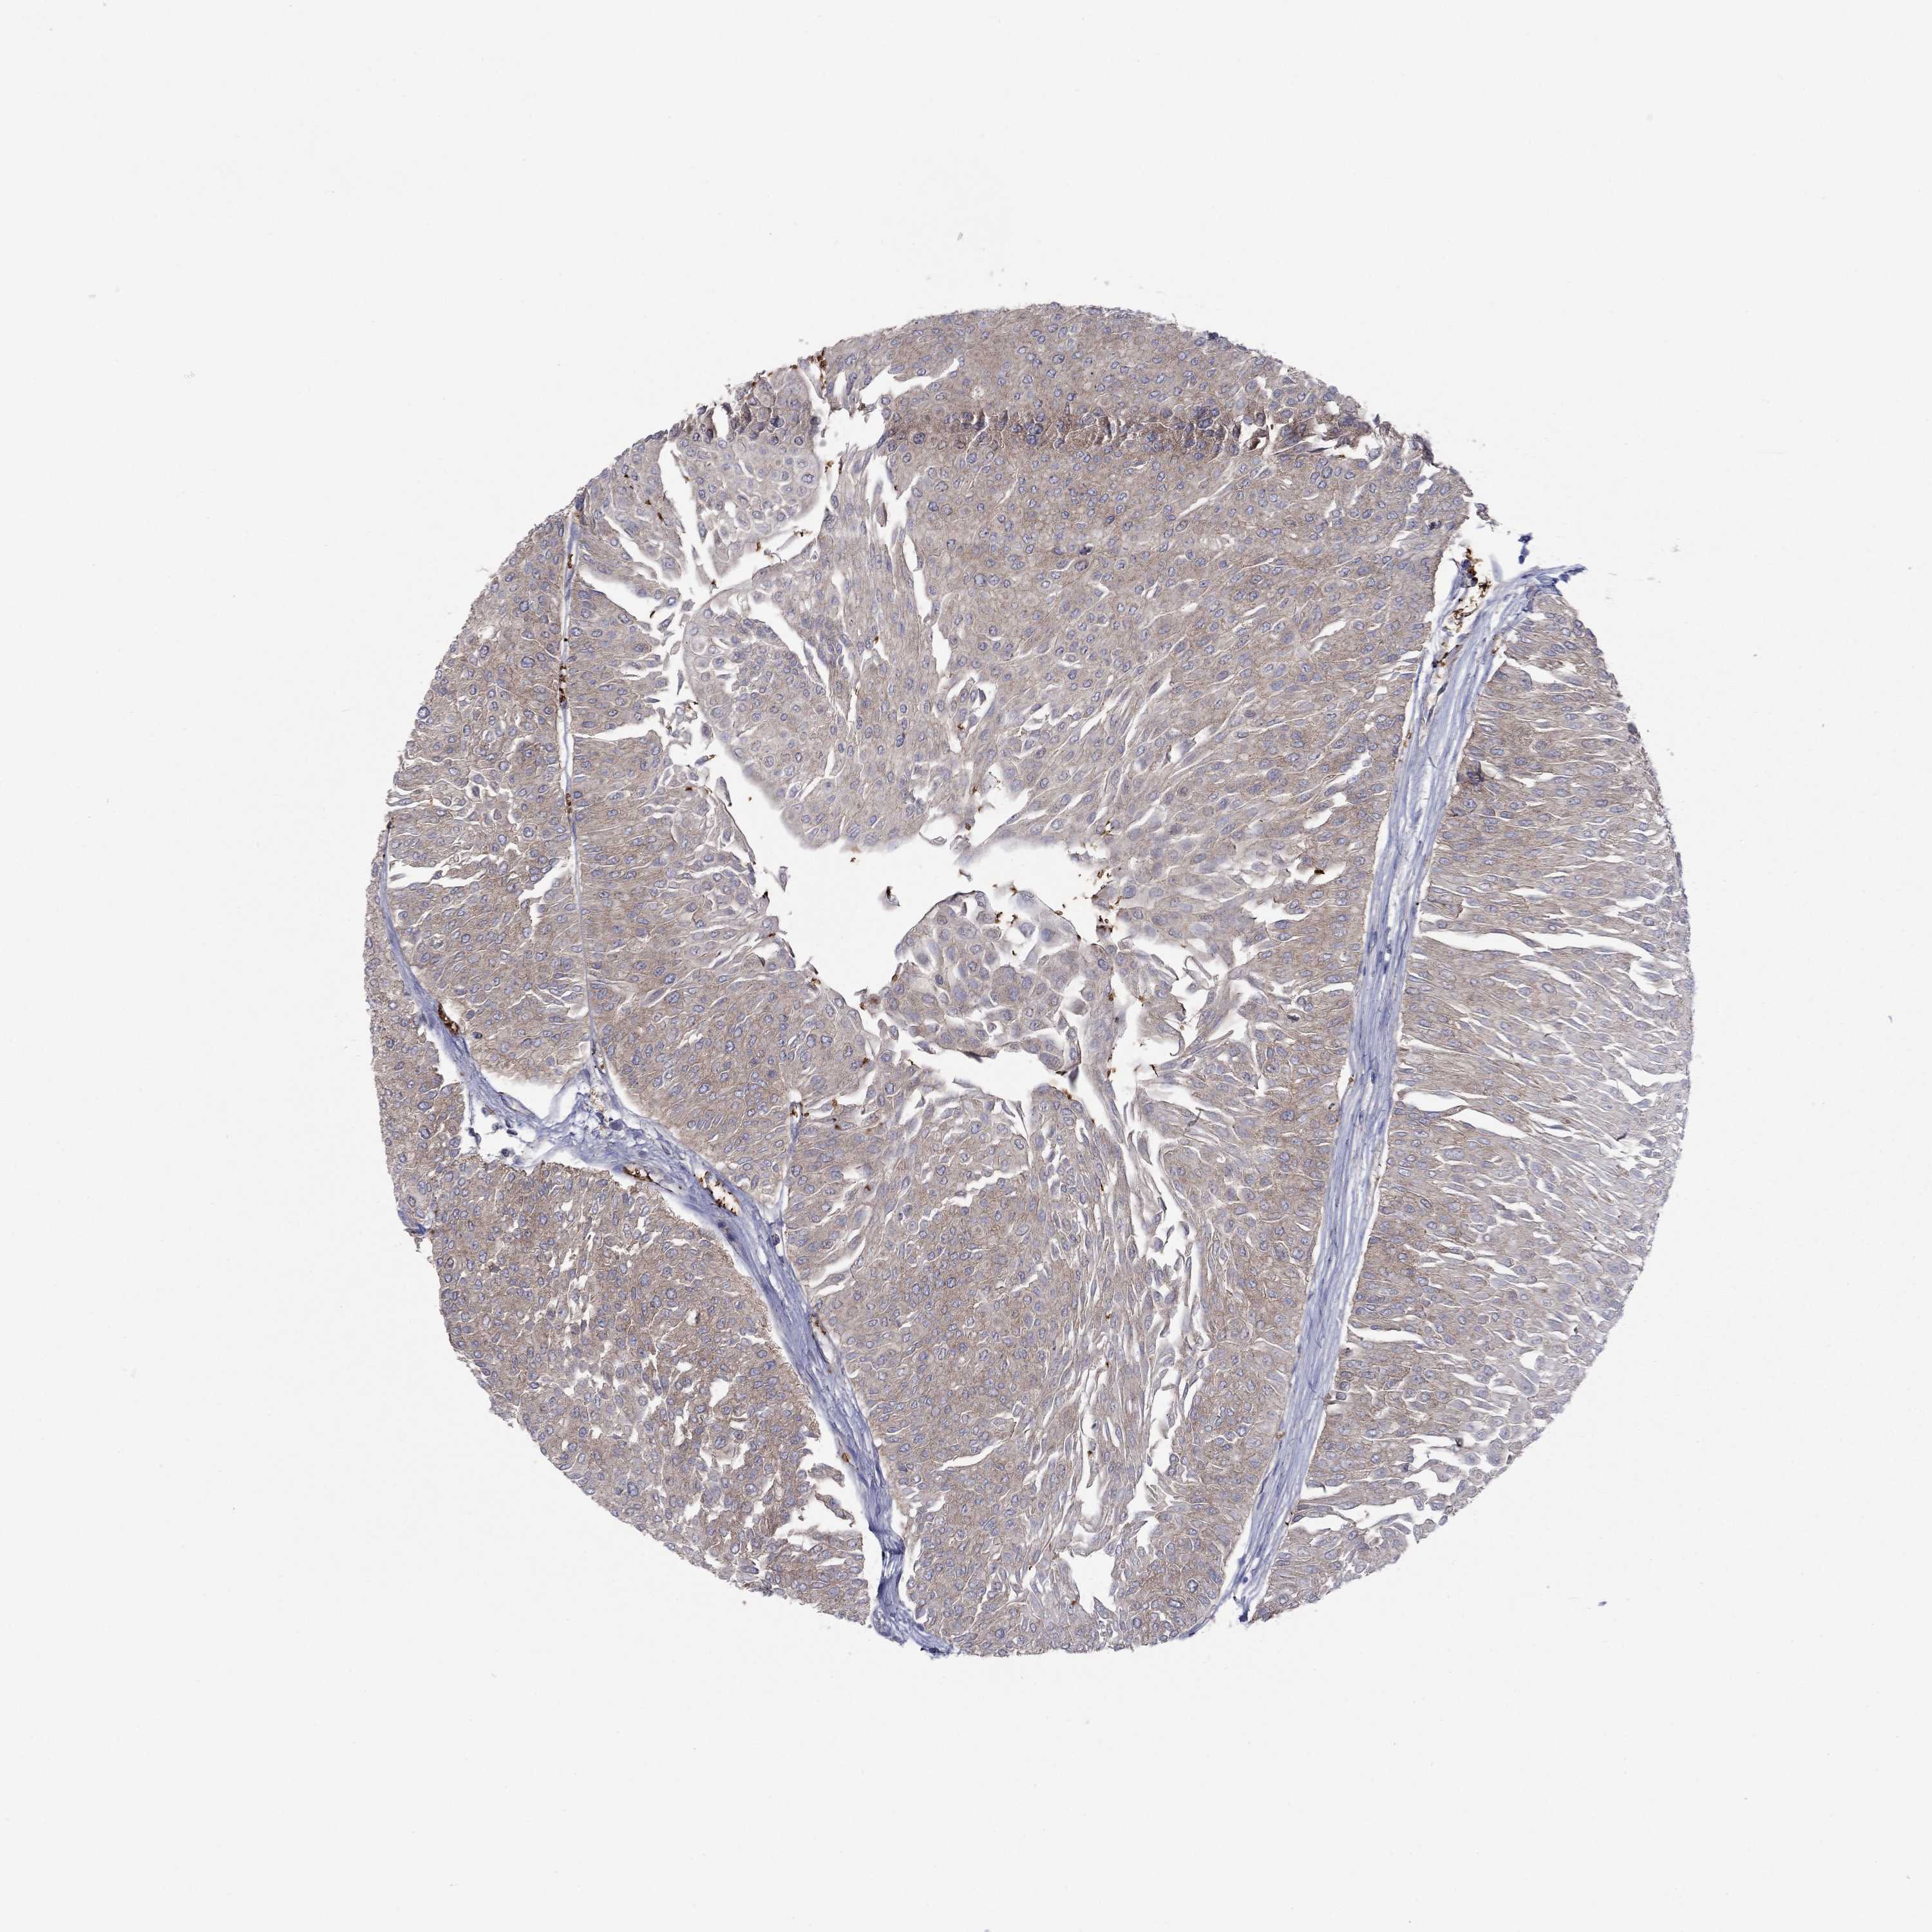

UROTHELIAL CANCER - Protein expressioni

A mouse-over function shows sample information and annotation data. Click on an image to view it in a full screen mode. Samples can be filtered based on level of antibody staining by selecting one or several of the following categories: high, medium, low and not detected. The assay and annotation is described here.

Note that samples used for immunohistochemistry by the Human Protein Atlas do not correspond to samples in the TCGA dataset.

Antibody stainingi

Antibody staining in the annotated cell types in the current human tissue is reported as not detected, low, medium, or high, based on conventional immunohistochemistry profiling in selected tissues. This score is based on the combination of the staining intensity and fraction of stained cells.

Each image is clickable and will lead to virtual microscopy that enables deeper exploration of all samples and also displays staining intensity scores, fraction scores and subcellular localization as well as patient and tissue information for each sample.

Antibody HPA065983

Antibody HPA071879

Staining

High

Medium

Low

Not detected

Intensity

Strong

Moderate

Weak

Negative

Quantity

>75%

75%-25%

<25%

None

Location

Nuclear

Cytoplasmic/membranous

Cytoplasmic/membranous,nuclear

Urothelial carcinoma, High grade

Urothelial carcinoma, Low grade